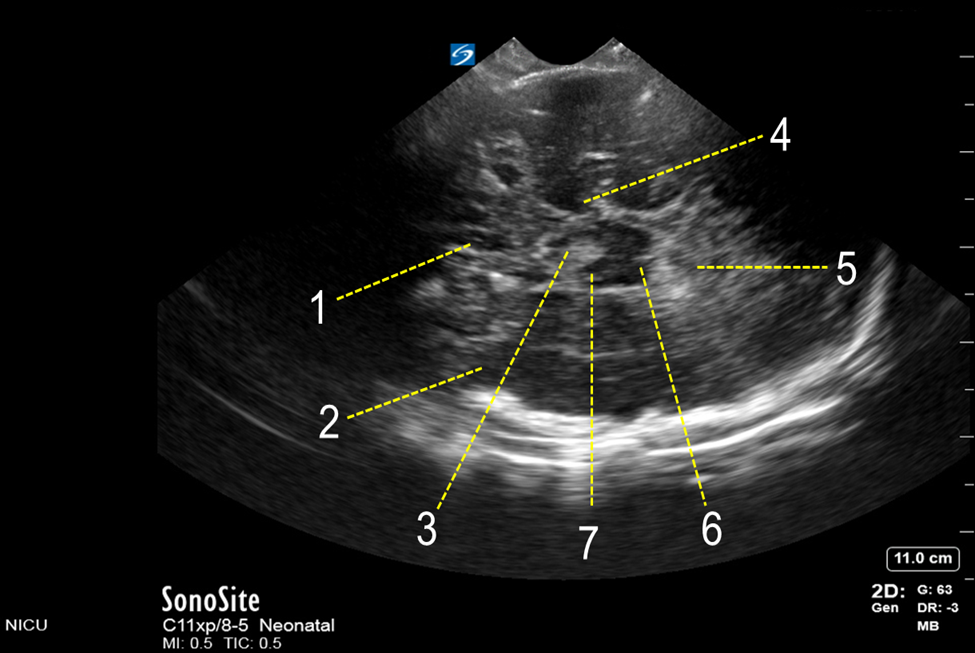

Neonatology Temporal Bone High Transverse View Image

1. Third Ventricle

2. Temporal Lobe

3. Interpeduncular Cistern

4. Temporal Horn of Lateral Ventricle

5. Cerebellar Vermis

6. Mesencephalon

7. Cerebral Peduncle